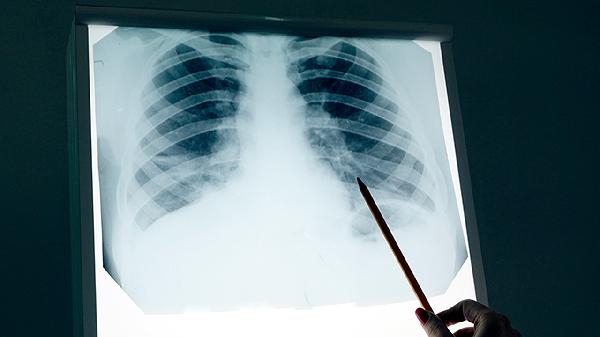

五、间质性肺病

间质性肺病是肺癌靶向治疗中一种相对少见但较为严重的副作用,患者可能出现进行性加重的呼吸困难、干咳和低氧血症。其发生可能与药物引起的肺部免疫炎症反应或直接肺损伤有关。一旦出现疑似症状,必须立即停药并就医。治疗通常需要大剂量糖皮质激素冲击,如使用甲泼尼龙片进行抗炎和免疫抑制治疗,并给予吸氧等呼吸支持。